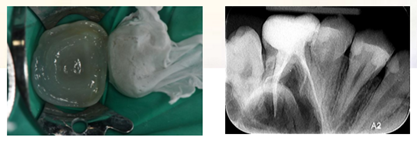

复诊:患者无不适,局麻下上橡皮障,去除暂封材料,结合3% NaClO冲洗,pathfile建立通路,TFA机用镍钛系统根管机械预备。根管荡洗,17%EDTA 溶液,生理盐水终末冲洗,因操作时间时间过长,氢氧化钙糊剂根管封药,玻璃离子暂封。

复诊,无不适,去除冠部暂封,试主牙胶尖,拍摄X-ray。

iROOT SP糊剂单尖法根充四根管,SDR树脂髓腔充填,拍摄X-ray,显示根管充填完好。